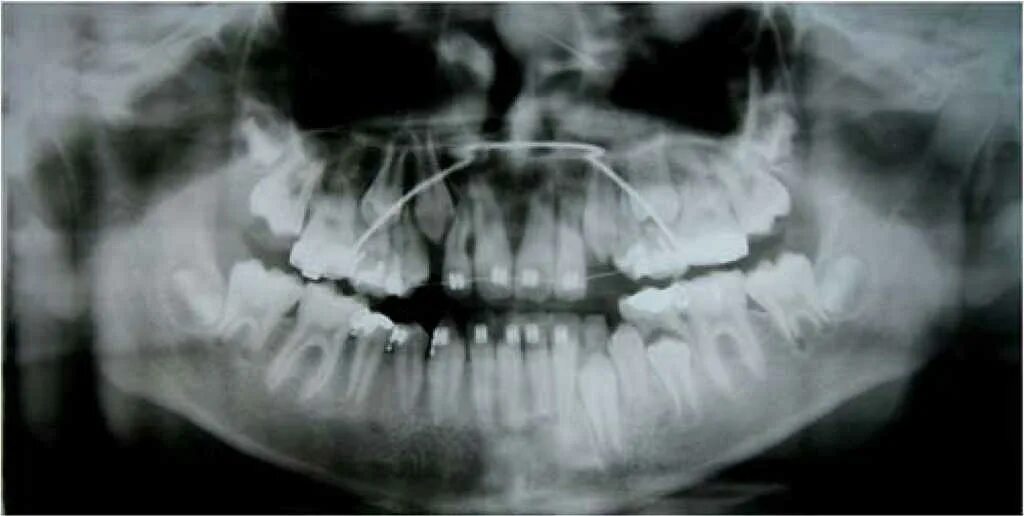

Сагиттальные аномалии окклюзии